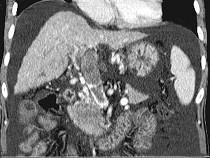

问题 女性,50岁,曾患乙型肝炎,肝硬化多年,右上腹胀痛1月余,CT检查如图所示,最全面的诊断是()

选项 A.肝硬化、腹水伴胆管细胞癌 B.肝硬化、腹水伴原发性肝癌 C.肝硬化、腹水、肝癌并门脉癌栓 D.肝硬化、腹水并肝脓肿 E.肝硬化、腹水并肝血管瘤

答案 C